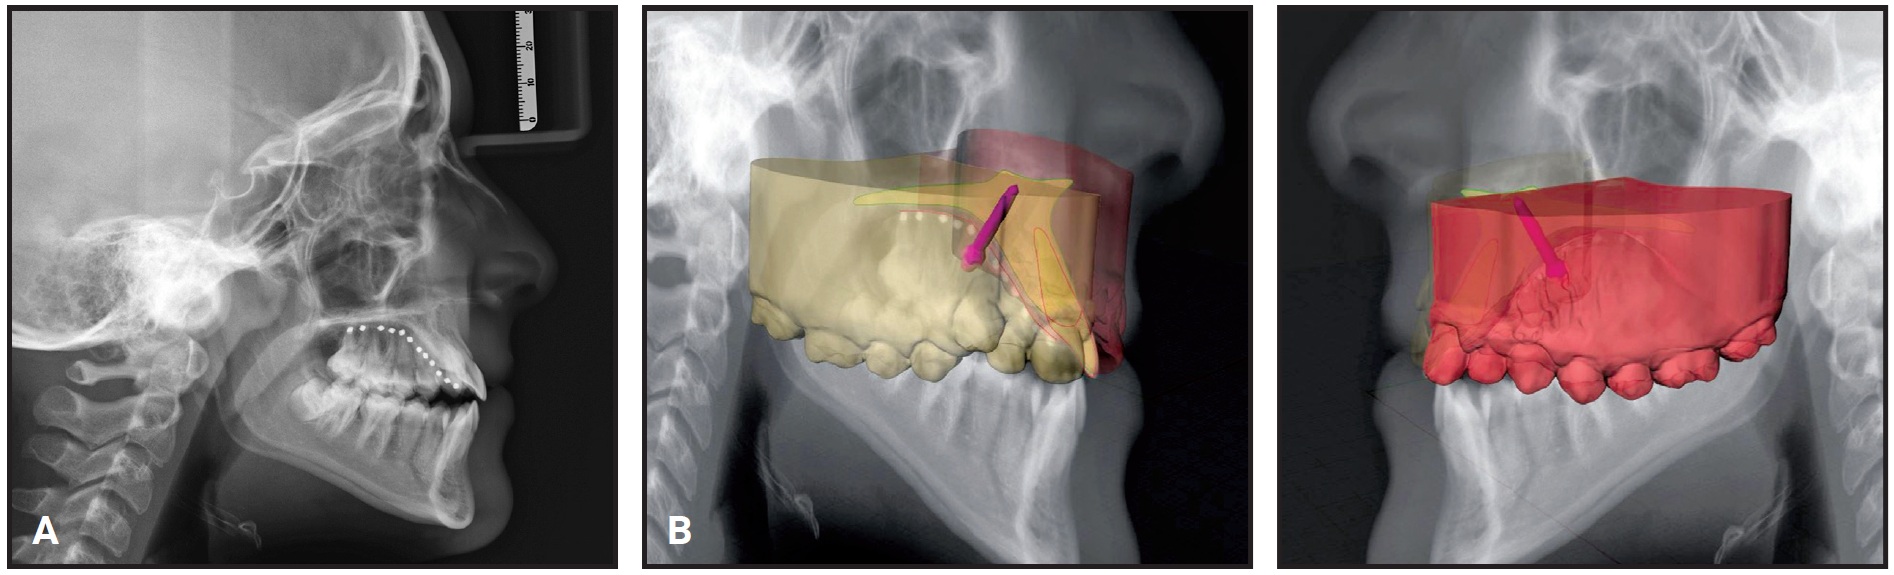

Fig. 11 A. Patient after 22 months of treatment. B. Superimposition of pretreatment (black) and post-treatment (red) cephalometric tracings.

The final panoramic radiograph showed good root parallelism and proper leveling of the interdental bone peaks, with no signs of root resorption. Cephalometric analysis (Table 1) confirmed an improvement in the skeletal sagittal discrepancy (ANB = 1.7°, Wits appraisal = –3.4mm), with an increased SNA angle (78.9°) and normalized lower-incisor inclination (IMPA = 92.5°). The vertical dimension was slightly increased (FMA = 29.8°, MP-SN = 39°), owing to clockwise rotation of the mandible. Regional superimpositions showed extrusion of the upper and lower molars and incisors, but the upper-molar extrusion was more limited than the upper-incisor extrusion, indicating that a clockwise rotation of the maxillary plane had compensated for the clockwise rotation of the mandible.

In our 14-year-old female patient, we decided to use an h-RPE with only a single phase of expansion (32 days) and concurrent facemask protraction. Stable skeletal anchorage, ensured by accurate miniscrew-insertion planning, allowed us to limit dentoalveolar effects such as mesialization of the upper first molars while maximizing the skeletal effect. Without the use of an Alt-RAMEC protocol to enhance the responsiveness of the maxilla, the orthopedic phase produced forward and downward maxillary displacement (SNA +2.1°, A-Na perp +1.7mm). Subsequent advancement of point A and retraction of pogonion (Pg-Na perp –3.2mm) were attributable primarily to clockwise rotation of the mandible (FMA +2.4°). This facemask-induced rotation could be identified as mandibular backward rotation type 2, as described by Björk, considering that a slight backward and upward growth of the condyles was observed.36 The increased vertical dimension and reduced chin projection improved the patient’s Class III facial profile. An orthodontic phase of fixed appliances and Class III elastics compensated for the mandibular rotation by extruding the anterior teeth, thus preventing the development of anterior open bite.